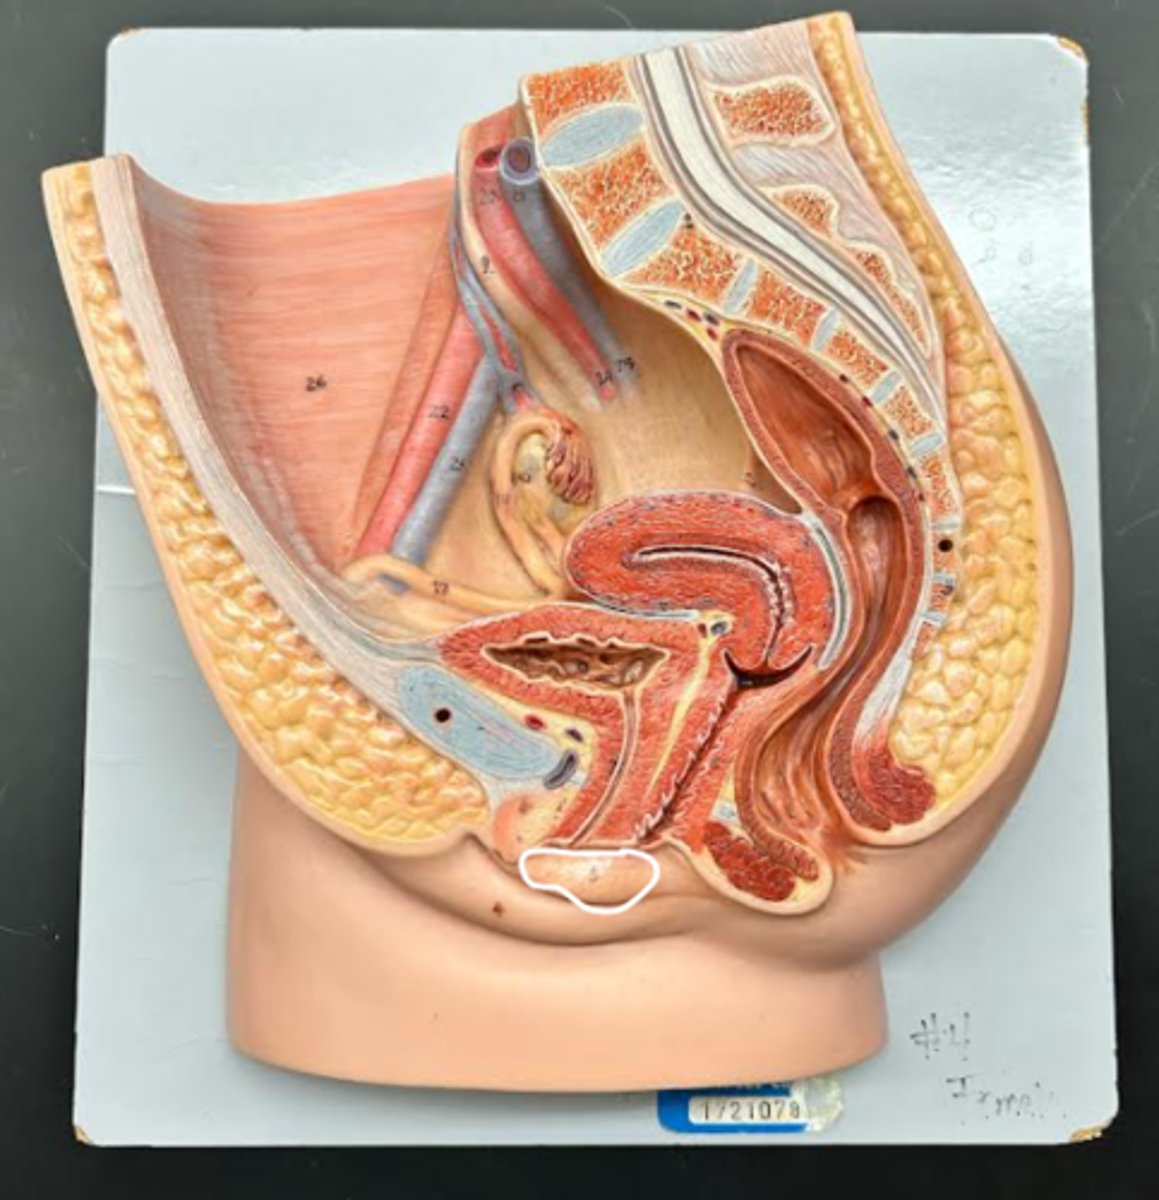

Clitoris

External urethral orifice